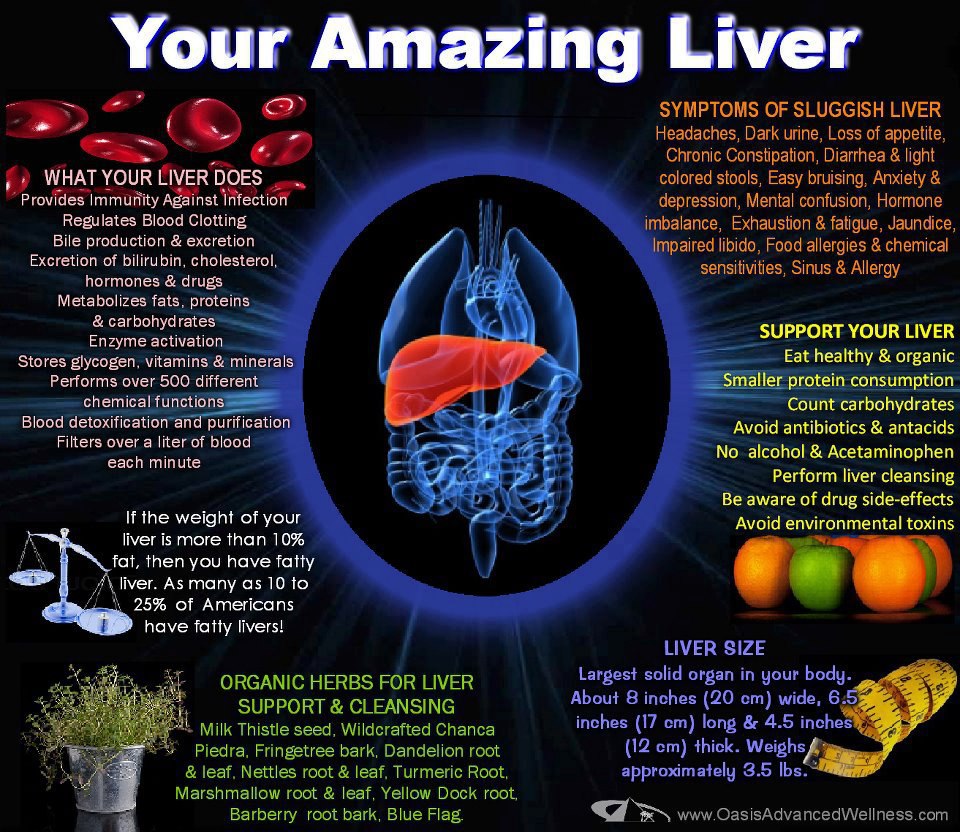

What is Fatty Liver? Do You Have It? | Fatty liver, Fatty, Refined carbs

A Posting by DR. RAMESH MANOCHA on LIVER and It’s Functions …

A Spike In Liver Disease Deaths Among Young Adults Fueled By Alcohol …

Gallery For > Fatty Liver Alcohol

Fatty Liver | Medical | Pinterest

Detox & Cleanse Your Liver: 25 Powerful Reasons for a Healthy Body! Dr. Mandell